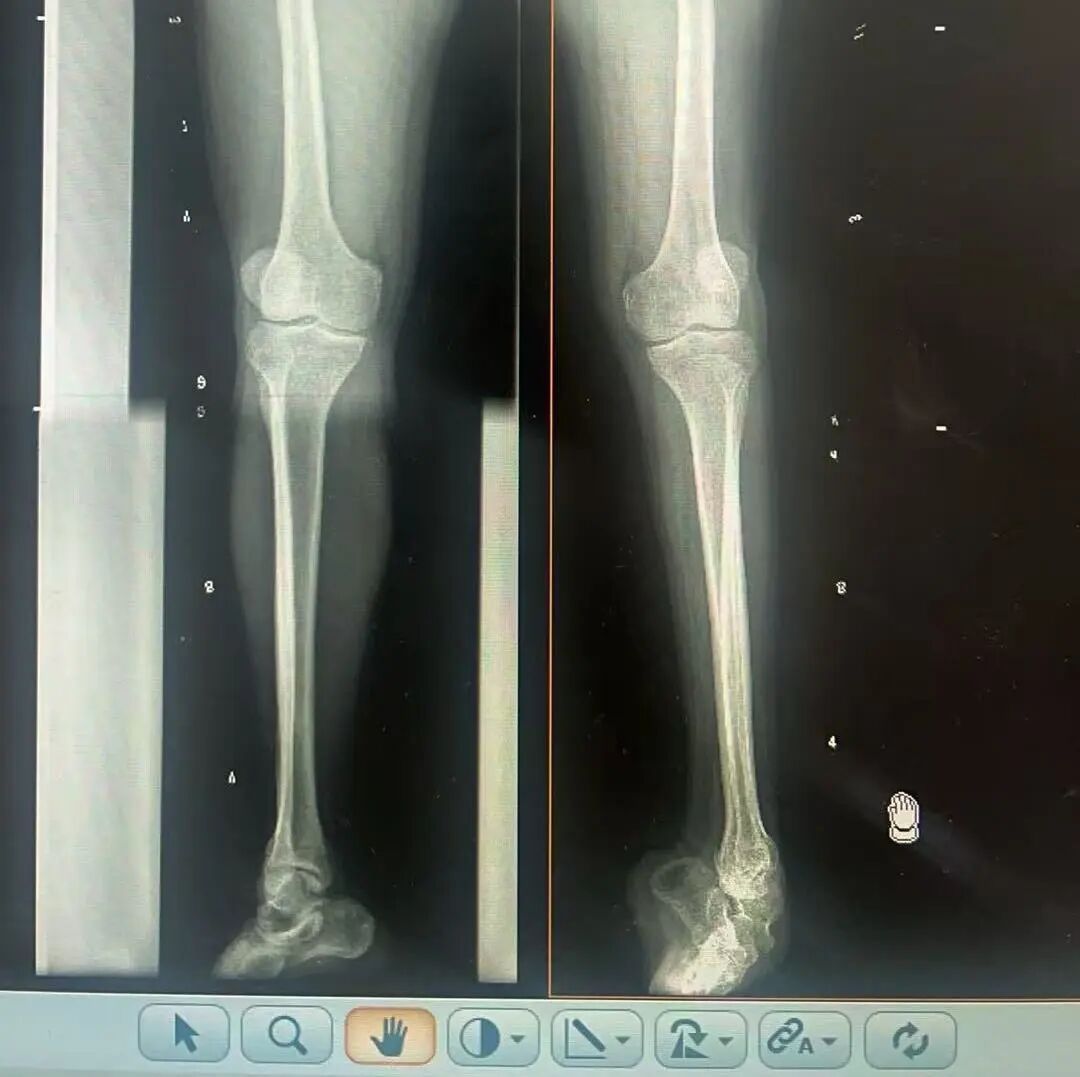

術(shù)前X光片 VS 術(shù)后治療效果

骨科隨即為陽先生進(jìn)行了全面的檢查。診斷明確而復(fù)雜:陽先生患有脊髓灰質(zhì)炎后遺癥、左踝馬蹄內(nèi)翻足、骨盆傾斜……面對這張沉甸甸的診斷書,由肢體功能重建顯微修復(fù)學(xué)科組長鄭群龍所帶領(lǐng)的醫(yī)療團(tuán)隊沒有畏懼,“這是一個家庭38年的堅守與期盼,我們必須全力以赴”

針對陽先生的復(fù)雜情況,鄭群龍醫(yī)師團(tuán)隊制定了詳盡的手術(shù)方案:左踝關(guān)節(jié)融合+馬蹄足畸形矯正+跟腱延長+外固定架固定術(shù)。手術(shù)的核心,正是伊里扎洛夫技術(shù)。這項技術(shù)如同精密的“時空建筑學(xué)”,通過微創(chuàng)安裝環(huán)形外固定架,前足-后足安裝鋼環(huán),再將足的鋼環(huán)與脛骨的固定鋼環(huán)在踝關(guān)節(jié)前、后、左、右用帶關(guān)節(jié)的螺紋桿連接,由此構(gòu)建成一個能體外牽拉調(diào)控的三維立體構(gòu)型,在術(shù)后進(jìn)行精準(zhǔn)、緩慢的調(diào)整,一寸一寸逐步將畸形的骨骼、軟組織恢復(fù)到正常位置。

9月1日,在全麻狀態(tài)下,陽先生接受了伊里扎洛夫外固定架安裝術(shù)。鄭群龍團(tuán)隊在陽先生左足足踝部植入克氏針及半針,安裝外固定架,通過支架的機(jī)械結(jié)構(gòu)對馬蹄內(nèi)翻畸形進(jìn)行緩慢、持續(xù)的牽拉矯正。術(shù)后,鄭群龍團(tuán)隊反復(fù)指導(dǎo)訓(xùn)練陽先生父子進(jìn)行外固定架的日常調(diào)試,按照預(yù)定計劃每日調(diào)整螺桿,逐漸糾正足部畸形,并配合專業(yè)的康復(fù)訓(xùn)練,包括踝關(guān)節(jié)主動及被動活動、下肢肌力訓(xùn)練等項目促進(jìn)陽先生腿部肢體功能恢復(fù),預(yù)防肌肉萎縮及關(guān)節(jié)僵硬。